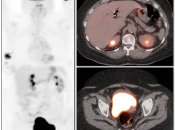

Extravasation of Injected FDG

FDG is injected intravenously. As many cancer patients have challenging venous access issues, partial extravasation of FDG during injection is not uncommon (an estimated 10% of patients have evidence of extravasation on their PET images).

Extravasation of FDG at the time of the intravenous injection can result in false positive interpretations due to:

- Focal intense uptake at the injection site.

- Linear uptake along the lymphatic channels within the arm (appearing as long vessels).

- Focal uptake in small ipsilateral axillary nodes.